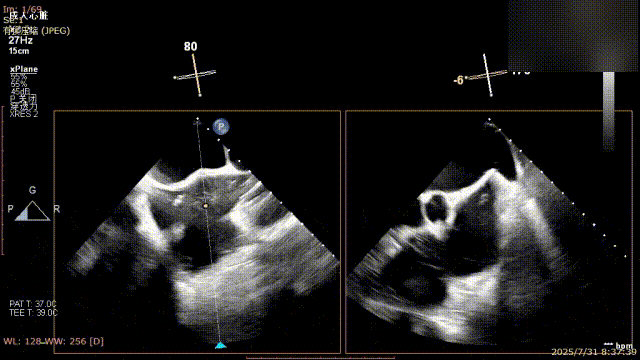

手术过程中,麻醉与围术期医学科副主任医师马金本确保麻醉过程平稳。心脏大血管外科主治医师董明亮穿刺股静脉置入血管鞘,并在心脏超声科梁皓主任及段福建教授TEE引导下,顺利穿刺房间隔,房间隔穿刺高度4.9cm。随后,在王安彪主任以及刘洋教授指导、心脏超声科梁皓主任TEE引导下,董明亮医师沿输送系统将延展呈“一字型”状态的国产夹合器送至左房,缓慢关闭夹合器并进行弹道测试。调整夹合器位置和方向后,董明亮医师再次将夹合器延展呈“一字型”完成跨瓣,避免发生腱索缠绕,成功捕获瓣叶后关闭夹合器,二尖瓣反流显著下降。夹合器完全解离后,超声示二尖瓣反流程度显著下降,残余反流0,平均跨瓣压差1mmHg,手术圆满成功。

房间隔穿刺

夹合器“一字型”状态进入左房